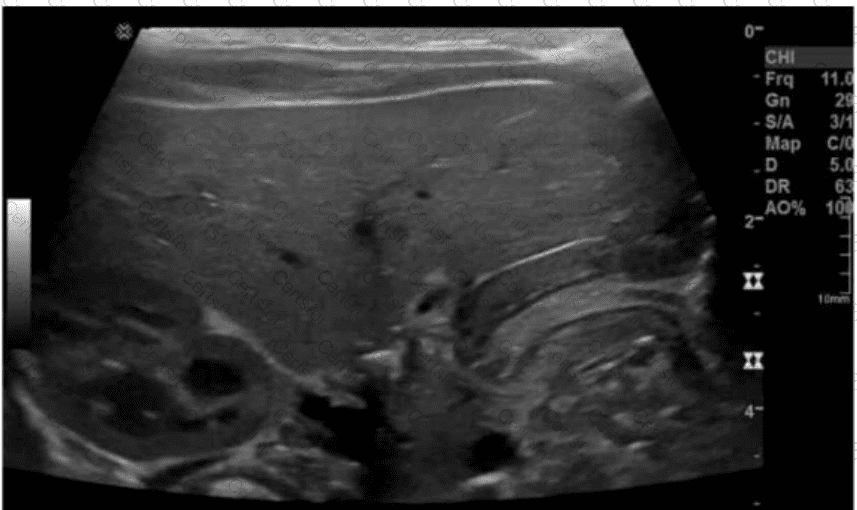

The ultrasound image clearly demonstrates a thickened and elongated pyloric muscle with a visible channel, which is characteristic of hypertrophic pyloric stenosis (HPS). This condition is most commonly seen in male infants between 2 and 8 weeks of age who present with non-bilious projectile vomiting, dehydration, and a palpable “olive-like” mass in the right upper quadrant.

Ultrasound is the imaging modality of choice and is highly sensitive and specific for diagnosing pyloric stenosis.

Key sonographic criteria for HPS:

Muscle thickness >3 mm

Pyloric channel length >15–17 mm

“Target sign” or “doughnut sign” on transverse imaging (concentric rings)

“Cervix” or “railroad track sign” on longitudinal imaging (elongated canal with echogenic center)